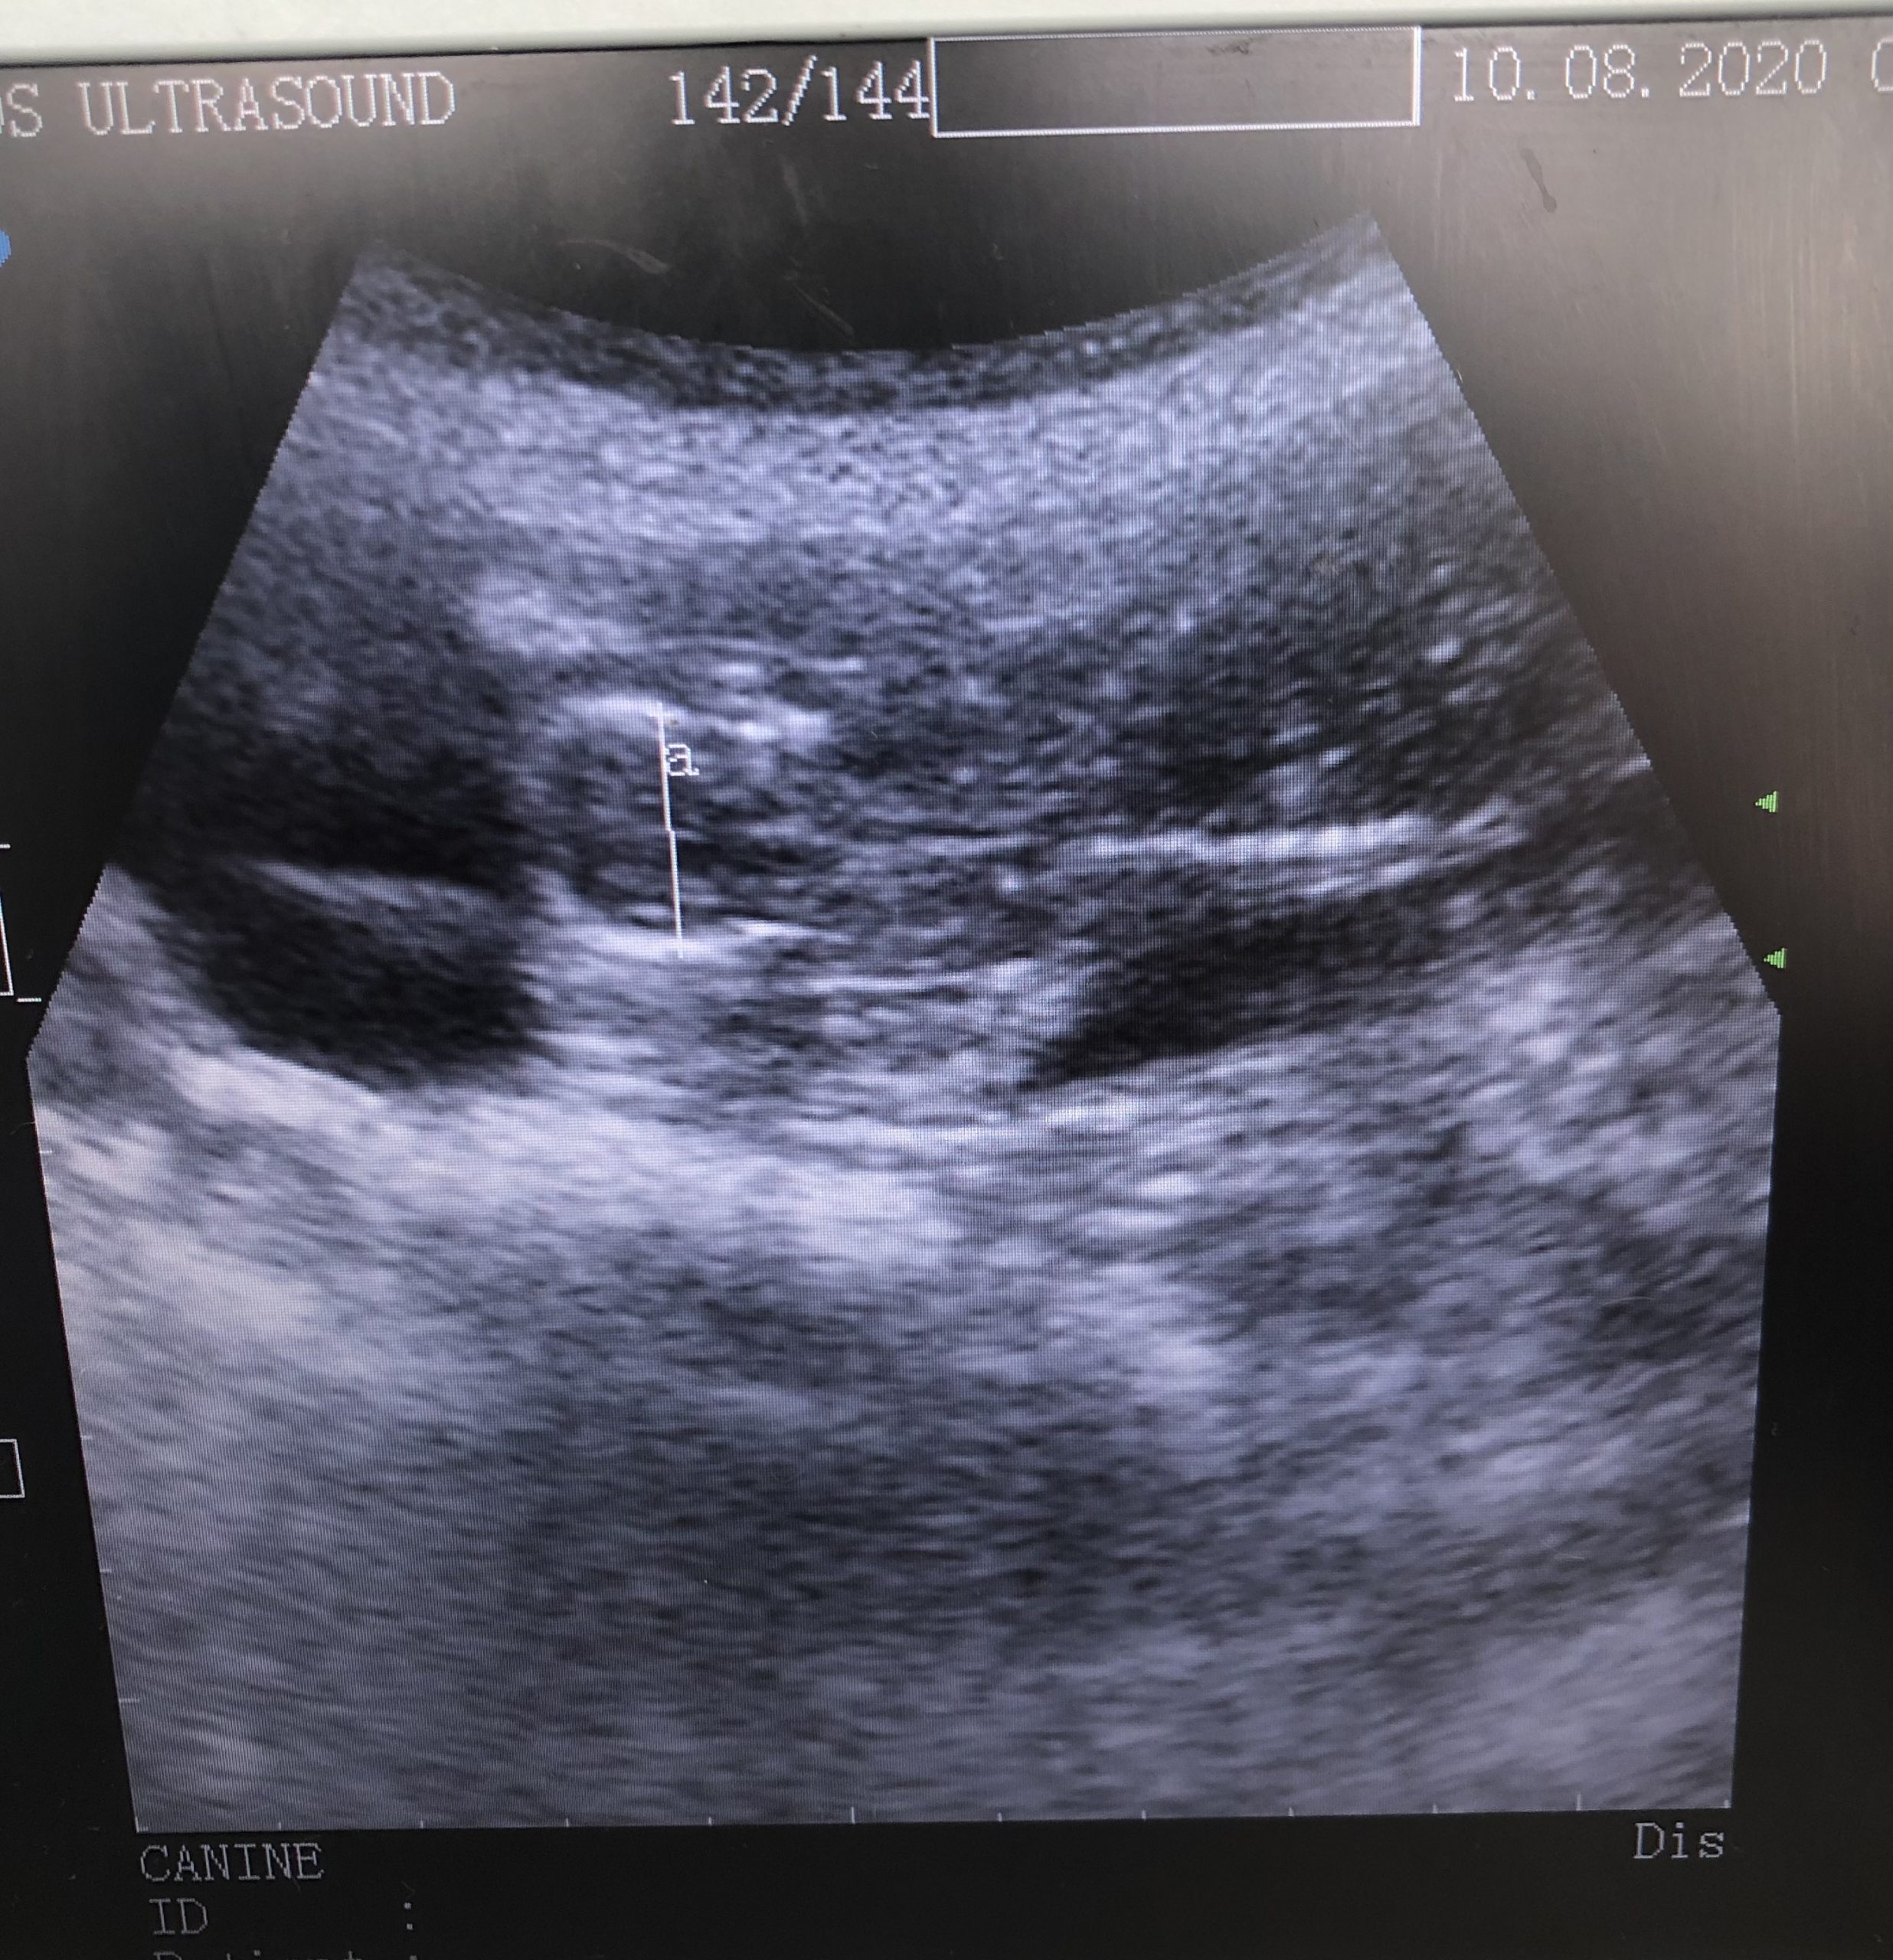

Black pug carrying 6+ puppies. Scull measurement 42 days gestation (2nd Image) she conceived on 1st mating.